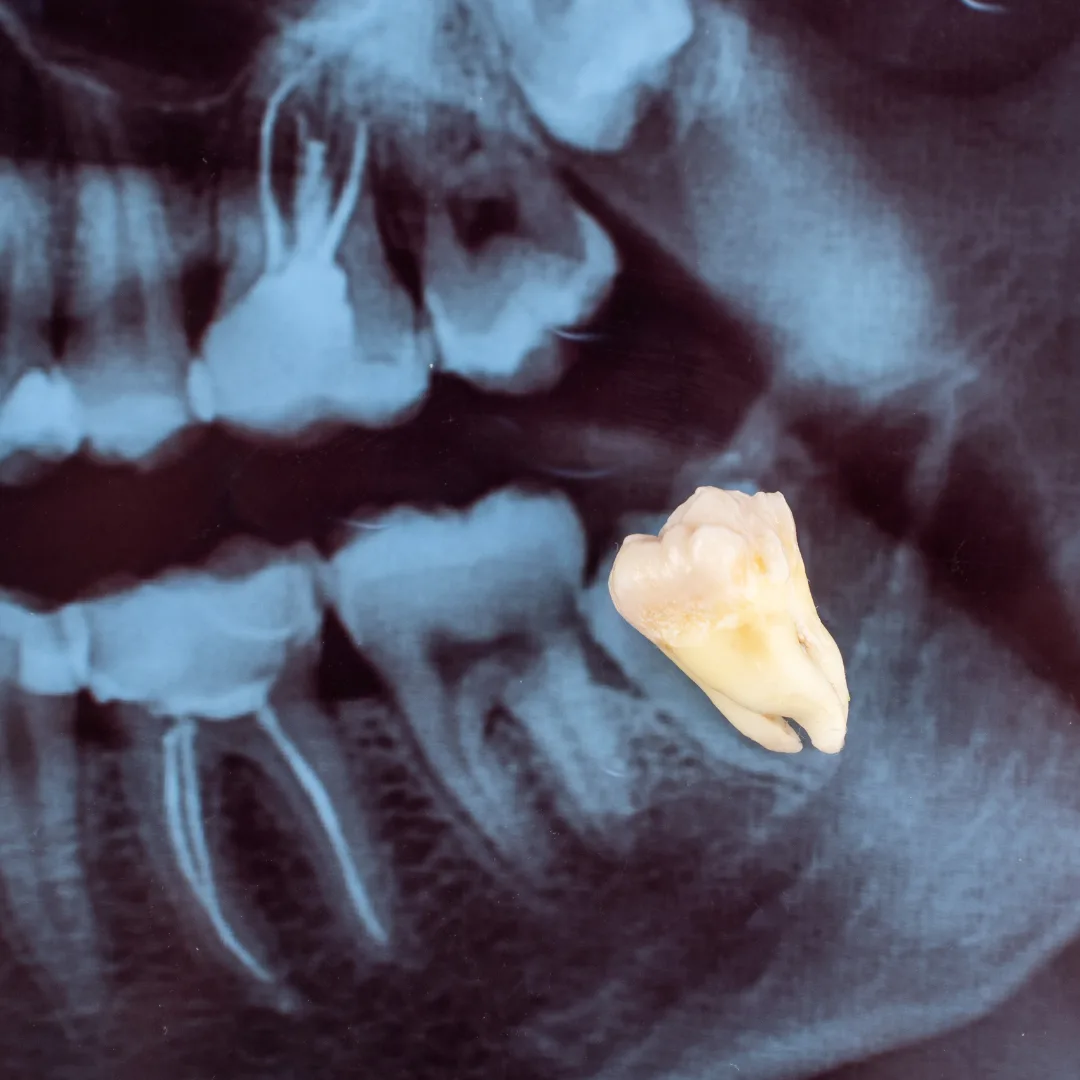

- Impacted Wisdom Teeth: Third molars are stuck under gum or bone, causing pain, infection, or crowding.

For impacted teeth or teeth with curved roots, we may perform a surgical extraction, which requires a small incision, removal of bone, and sometimes division of the tooth into sections for easier removal. Surgical extractions may require a few stitches.

A simple extraction is for teeth that are visible and loose enough to be removed with forceps. A surgical extraction is for teeth that are impacted, broken below the gum line, or have curved roots. Both are performed gently; surgical extractions may require a small incision and stitches.